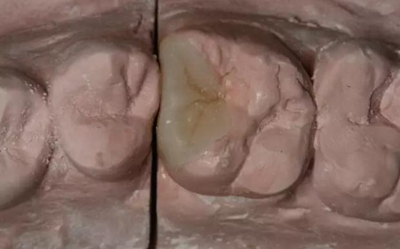

患者男性,35歲,B6銀汞充填后食物嵌塞,要求重新充填,口內(nèi)檢查見B6近中鄰頜面銀汞充填物,局部缺損,有繼發(fā)齲,去除原充填物及繼發(fā)齲,發(fā)現(xiàn)齲壞位于牙齦下方,給予冠延長手術,同期嵌體預備,后一次性取模。(同樣設計為齦上邊緣)

硅橡膠取模后,灌注模型,科爾琥珀樹脂制作嵌體。

一周后拆線,口內(nèi)試戴合適,粘結嵌體。